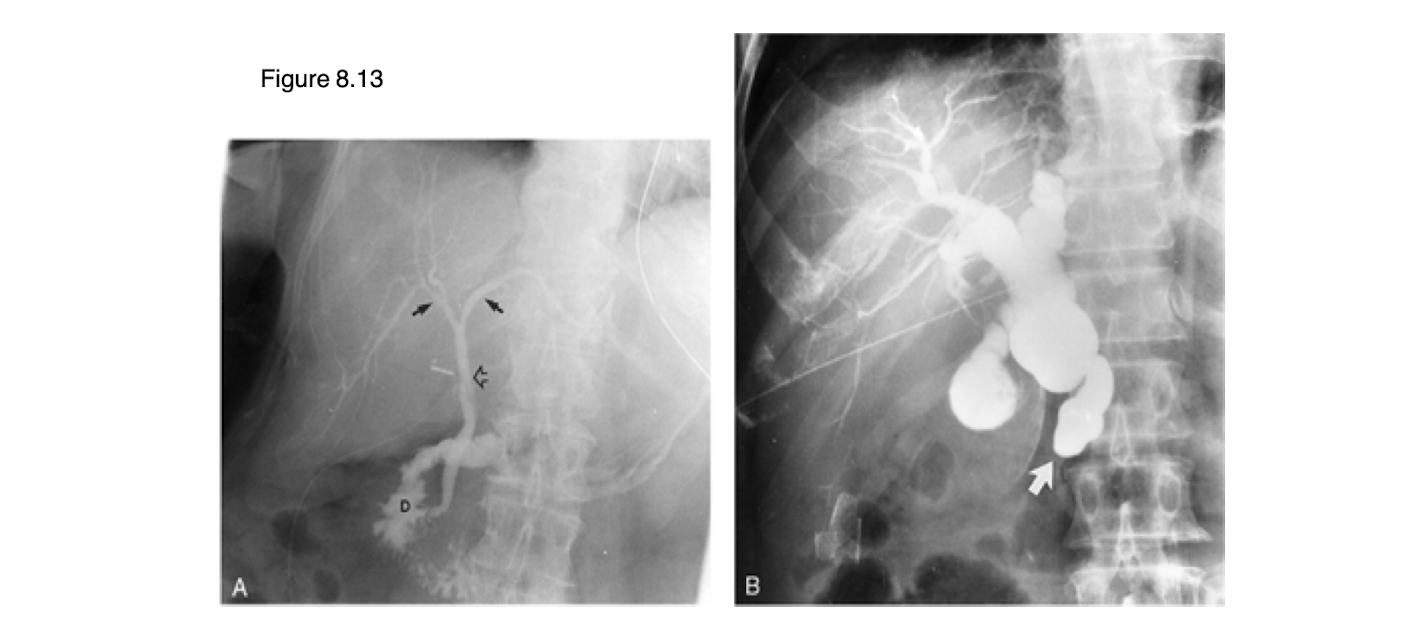

What is shown on the image?

Diverticulum

What are the images showing?

strictures